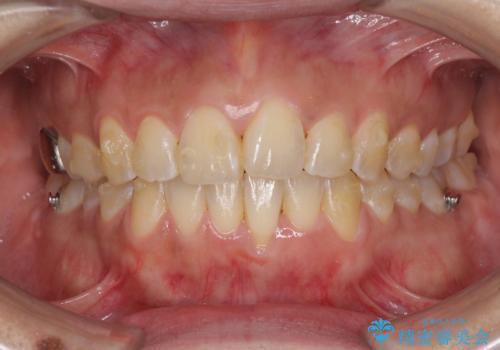

インビザラインによる狭窄歯列の拡大矯正

- 前歯のデコボコを治したいとのことで来院された患者様です。

上下顎ともに歯列全体の後方移動と側方拡大、IPR(歯と歯の間を削る)によってデコボコが解消するように設計し、インビザラインにより治療を行うこととしました。

後方移動に際し、上下の親知らずは4本とも抜歯することとしました。

治療途中で関西に転勤となってしまったため、東京に出張で来るタイミングに合わせて治療を進めることになりました。そのため、治療期間が長くなってしまいましたが、無事に仕上げることができました。